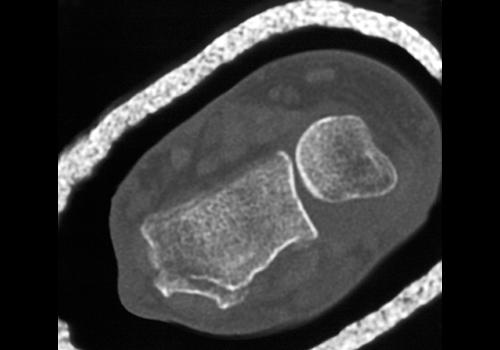

Intra-articular extension is reported to occur in 50-81% of distal radius fractures. If identified, a detailed description of the location and appearance must be provided. The radiocarpal articulation (at the scaphoid and lunate fossa), the radioulnar articulation (at the sigmoid notch) or the ulnar styloid may be involved. Careful inspection must be made to detect any step-off in the articular region of the radiocarpal joint or gaps, because these have prognostic value for the development of radiocarpal osteoarthritis. The presence of articular incongruities measuring more than 1-2 mm after closed reduction is felt by many to be an indication for surgical reduction to prevent disabling osteoarthritis an d maintain wrist function. CT has been shown to be superior for measuring the articular gapping, with substantially larger measurements compared to radiographs. Furthermore, radiographs underestimate the degree of comminution and DRUJ involvement. With respect to articular step-offs, one study by Katz showed no significant difference between CT and radiographs for quantification; however, Pruitt demonstrated that determination of t he extent of articular surface depression was better with CT.

Extraarticular malunion of distal radius fractures manifests by number of factors, which can be identified with CT and should be assessed by the radiologist both pre and post reduction. These findings may dictate the need for surgical reduction if they are present following closed reduction. Radial shortening results in DRUJ osteoarthritis and DRUJ dysfunction. As little as 2.5 mm will increase the ulnar load, and 6 mm results in clinical symptoms. A decrease in radial inclination (more than 5 degree loss) contributes to DRUJ dysfunction. A change in the volar tilt is an additional parameter. A loss of volar tilt of more than 10 degrees is felt to be an indication for reduction. This angulation also increases ulnar load and impacts DRUJ mechanics.

For intraarticular malunion, the most significant factor is articular incongruity. Gap displacement or the presence of step-off displacement contribute to the development of osteoarthritis. Following closed reduction, if displacements of more than 1-2 mm are identified, surgery is commonly performed. Because helical CT has been shown to be superior to radiographs for quantitization of these gaps, narrow collimation MDCT should provide even more accurate measurements such small regions of diastasis, regardless of the fracture orientation.